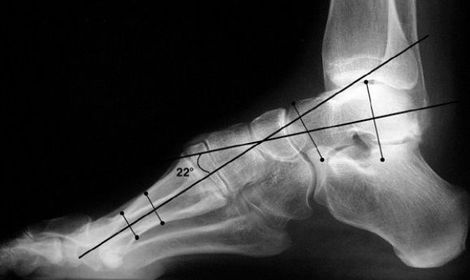

What is this angle called? What foot type does it indicate | Talar - 1st MT or Meary's Angle Pes cavo-varus |

What is this angle called? What is normal? What does an increased angle indicate? | Talo-calcaneal angle. 25-45 degrees. Increased angle = hindfoot valgus |